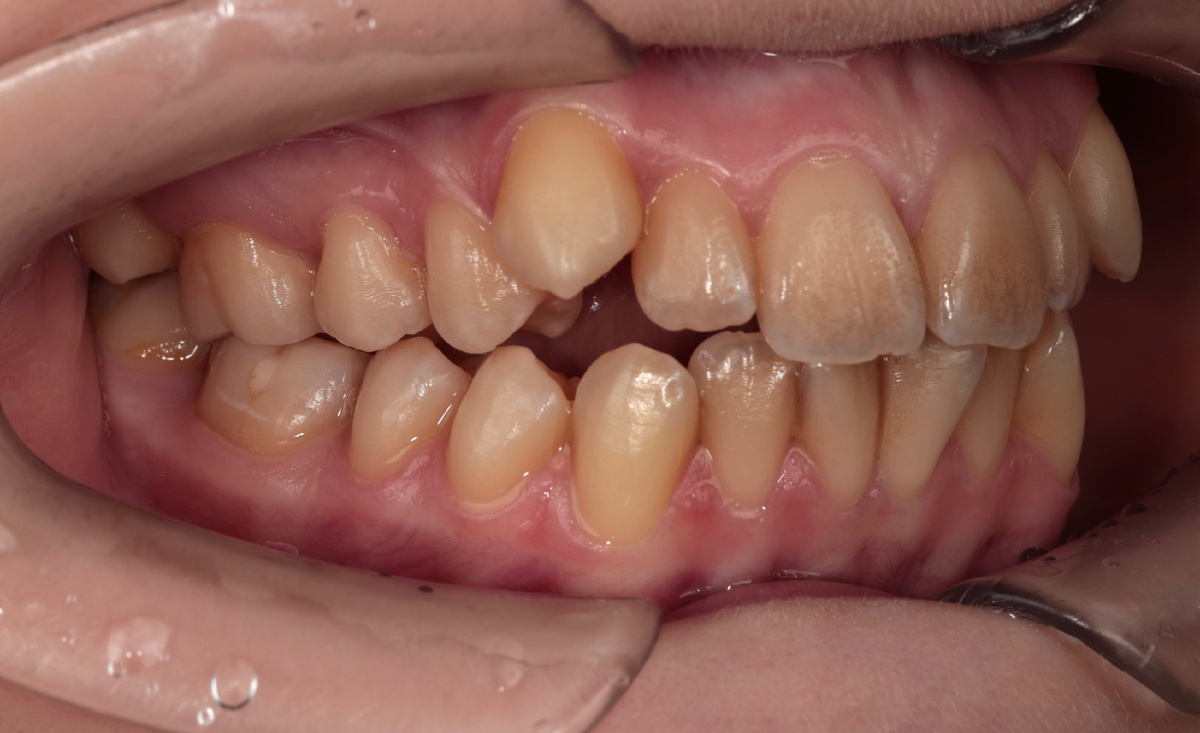

Три месяца назад поставили брекеты подростку с "вампирскими" клыками. Вестибулярное супраположение - так это называется научно. А по-простому - клыки растут поверх других зубов, торчат вперёд и вверх. Сегодня покажу промежуточный результат. Всего 3 месяца прошло, а клыки уже почти в зубном ряду нанормальных позициях. Даже непрофессионал увидит разницу, эта патология стабильно радует эффектным и быстрым преображением улыбки. Но это только начало пути, впереди ещё 1,5-2 года работы. Расскажу, почему так долго и что будет дальше. Вестибулярное супраположение клыков - одна из распространённых ортодонтических патологий. Клыки прорезываются одними из последних постоянных зубов (позже только вторые моляры и зубы мудрости). К моменту их появления места в челюсти, случается, маловато бывает. Все хорошие места заняты более расторопными собратьями. И что же остаётся клыку делать? Прорезываться там, где получится. Обычно - выше линии улыбки, поверх других зубов. Получается та самая "вампирская" у

Три месяца назад поставили брекеты подростку с "вампирскими" клыками. Вестибулярное супраположение - так это называется научно. А по-простому - клыки растут поверх других зубов, торчат вперёд и вверх.

Вестибулярное супраположение клыков - одна из распространённых ортодонтических патологий. Клыки прорезываются одними из последних постоянных зубов (позже только вторые моляры и зубы мудрости). К моменту их появления места в челюсти, случается, маловато бывает. Все хорошие места заняты более расторопными собратьями.

И что же остаётся клыку делать? Прорезываться там, где получится. Обычно - выше линии улыбки, поверх других зубов. Получается та самая "вампирская" улыбка.

Как выглядит типичный пациент с "вампирскими" клыками - знакомы такие?